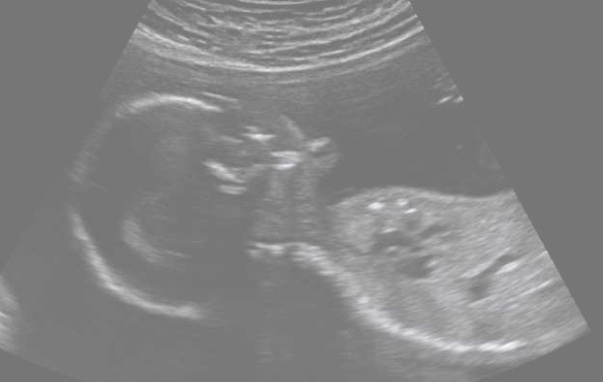

They lived in a warm watery wonderland.

Nick grew so big that him and Pops bodies were pressed together everyday in a squishy cuddle.